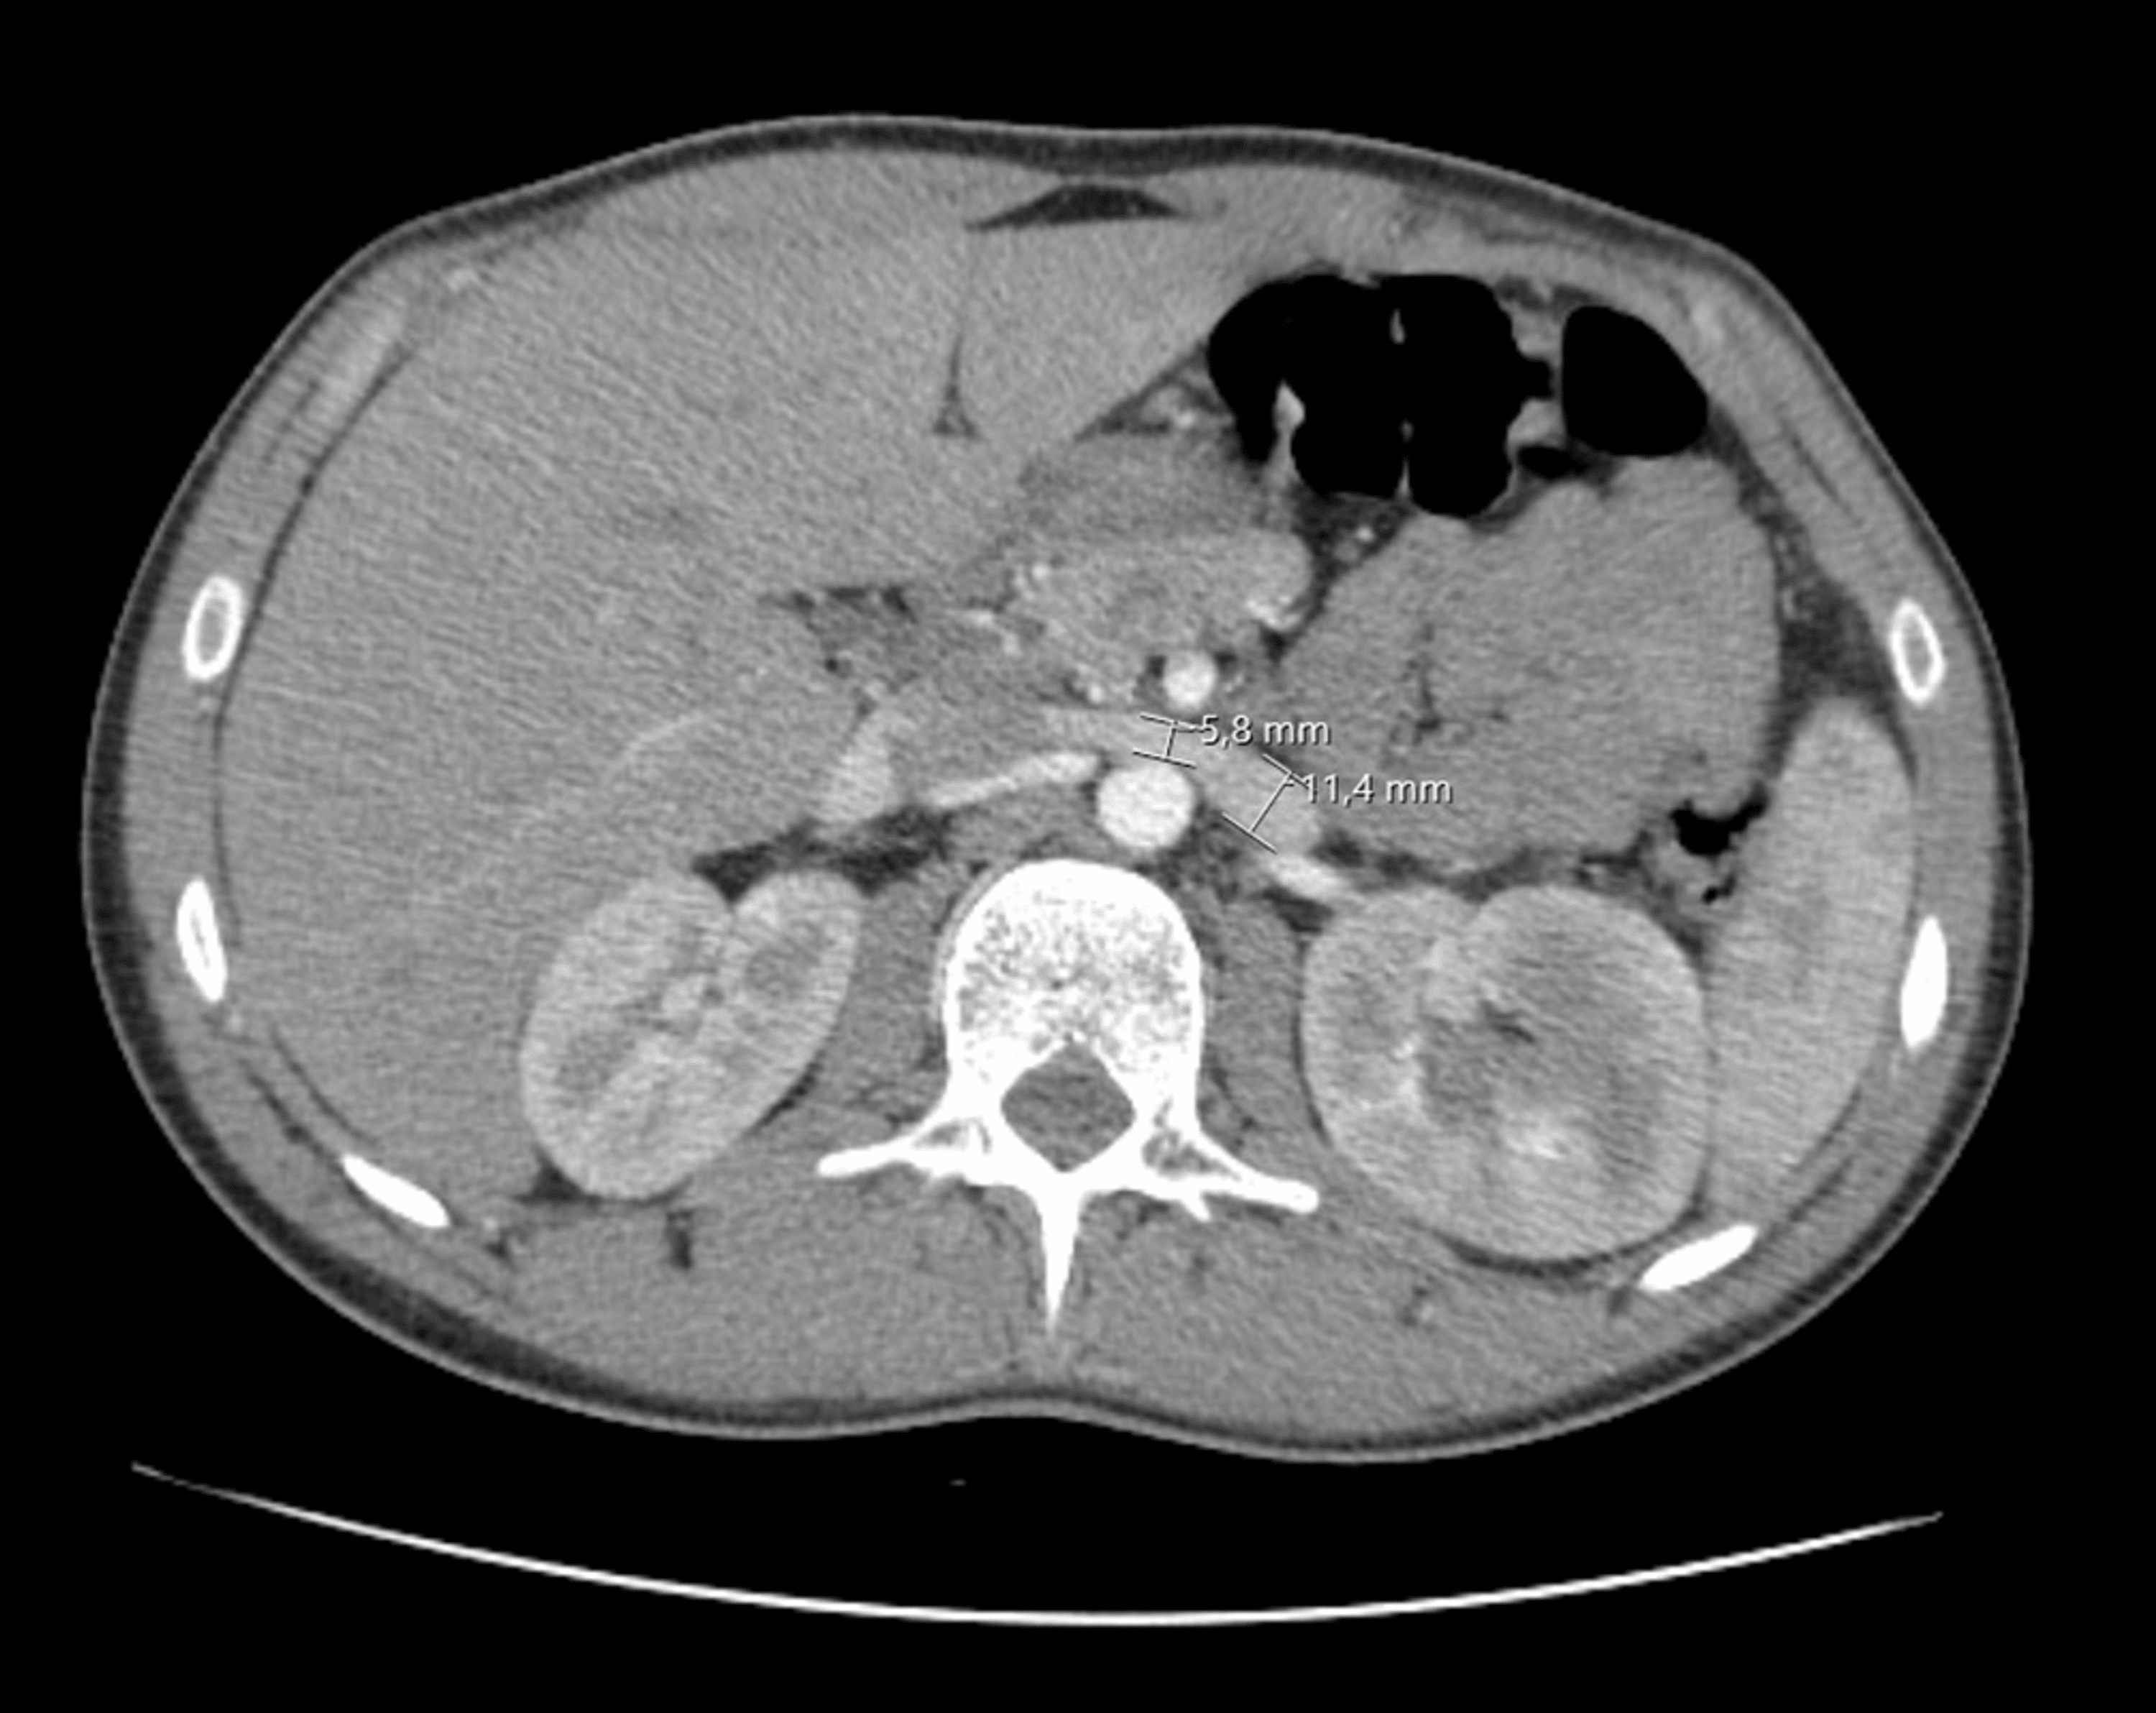

CT angiography of a patient with "the nutcracker syndrome" Download Nutcracker Syndrome Back Pain Nutcracker syndrome (ncs) is an extrinsic compression of the left renal vein (lrv) by the superior mesenteric artery (sma). The nutcracker syndrome is a rare and often unrecognized cause of chronic pelvic pain and left back pain. Nutcracker syndrome (ncs) is a rare condition characterized by a group of clinical manifestations, like hematuria and pain, and is. This phenomenon can. Nutcracker Syndrome Back Pain.

From www.veinspecialists.com